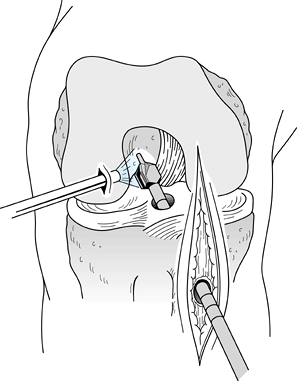

After removing the graft from its gauze, place a two-pronged pusher at the base of the femoral bone plug (Fig. 89.20) and position a curved hemostat through

P.2367

the inferomedial portal with its tips pointed up. Then “push up” the

graft through the tibial tunnel and grasp it with the hemostat at the

junction of the proximal and middle third of the bone plug (Fig. 89.21A). Remove the pusher and guide the graft up into the femoral socket (Fig. 89.21B). Orient the cortical surface of the femoral plug posteriorly and in the coronal plane.

Figure 89.20.

Illustration of a right knee. Use a two-pronged pusher to guide the

graft up the tibial tunnel. Remove the pusher from the tunnel before

the tibial bone plug enters its tunnel, however, or the pusher will be

difficult to remove. (Redrawn from Hardin GT, Bach BR Jr, Bush-Joseph

CA, Farr J. Endoscopic Single-Incision Anterior Cruciate Ligament

Reconstruction Using Patellar Tendon Autograft. Surgical Technique. Am J Knee Surg 1992;5:144.)

Figure 89.21. Arthroscopic views of the right knee. A: Grasp the femoral bone plug with a curved hemostat placed through the inferomedial portal with tip pointed up. B: Then guide the graft up into the femoral socket. C:

Once the plug is seated roughly 85% into its socket, place a Nitenol

Hyperflex guide pin at the 11 o’clock position of the graft. Hyperflex

the knee and gently push the pin to the back of the socket. D: Place the satellite pusher at the inferior edge of the femoral bone plug and tap the plug to seat it fully in its socket. -